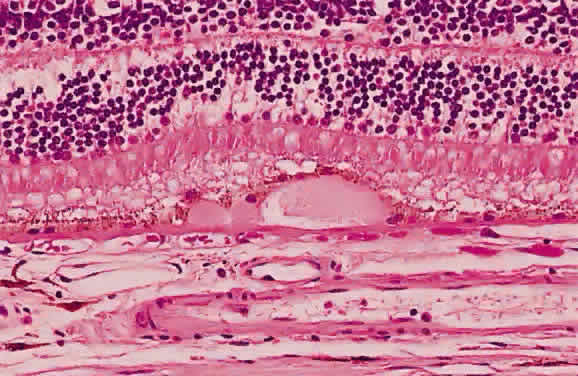

Fig. 24. A. Histologic section of cytomegalic inclusion retinitis. The characteristic inclusions cannot be seen at this magnification. Compare the appearance of viable healthy retina (left of arrow) with necrotic retina (right of arrow). The admixture of necrotic retina (clinically white) with hemorrhage (clinically red) accounts for the ophthalmoscopic appearance of this entity. B. Cytomegalovirus retinitis. Histologic section of sensory retina demonstrating massive necrosis involving all layers. (Courtesy of Ralph C. Eagle Jr, MD, Philadelphia, PA)